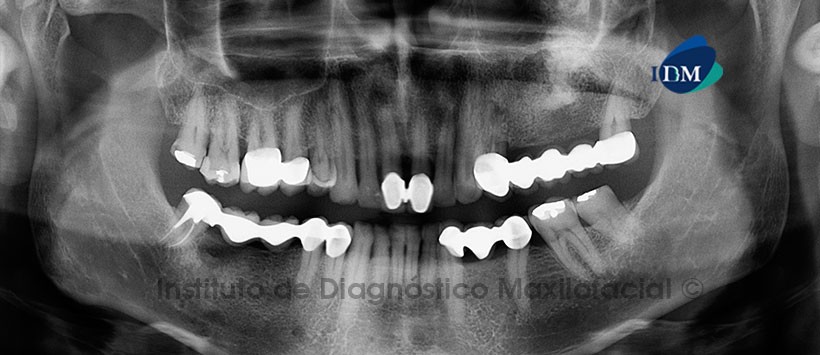

Paciente masculino de 55 años de edad que es referido para el estudio imagenológico a consecuencia de un leve dolor a nivel del maxilar superior del lado izquierdo; así mismo, manifiesta haber sido intervenido (40 años atrás) por presentar un tumor en la misma zona. A la evaluación de la radiografía panorámica se observa la presencia de una imagen radiopaca de límites difusos proyectada sobre  el seno maxilar y el proceso alveolar del lado de interés (Fig. 1).

La tomografía computarizada de haz cónico mediante la reconstrucción multiplanar muestra de manera más clara una lesión radiopaca que compromete la pared basal del seno maxilar y ocasiona la expansión de la tabla ósea bucal y palatina. En la misma zona se aprecia una estructura ósea dependiente de las paredes lateral y medial del seno  maxilar, asociada al engrosamiento de la mucosa sinusal circundante (Fig. 2).  En los cortes transaxiales y tangenciales se evidencia la discontinuidad de la pared lateral del mencionado seno; así como, la localización central de la estructura ósea (Fig. 3 y 4). Signos imagenológicos compatibles con una Lesión Fibroósea asociada a una secuela posquirúrgica.